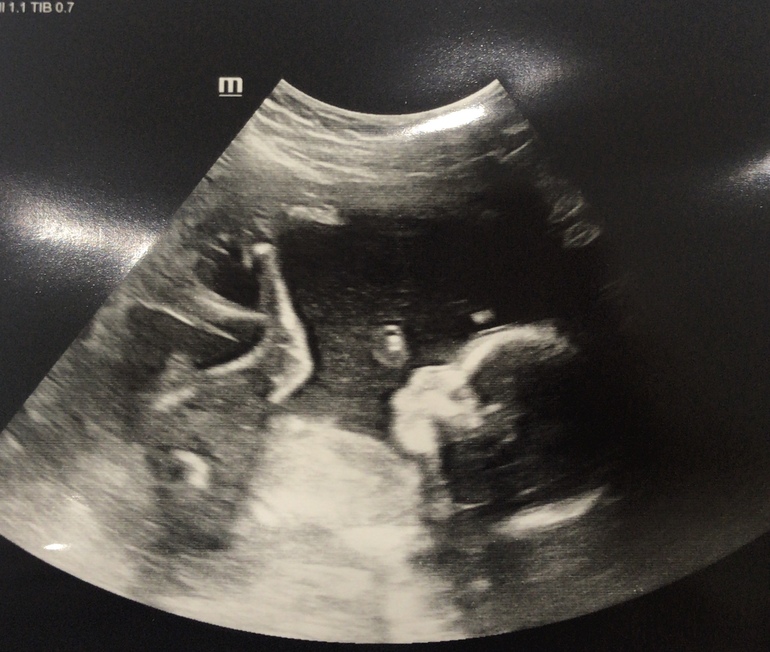

2 скрининг (фото малыша)

Второй триместрНу что, не дождавшись записи на субботу, приехала я делать скрининг в 19 недель и 4 дня.

Малыш растёт и развивается хорошо. Ура!

Весит уже 300 грамм!

Все показатели в норме! Фуф 😅